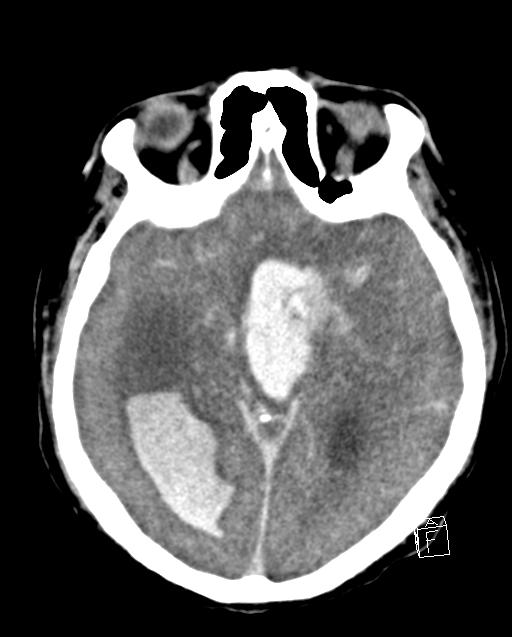

- Intracranial haemorrhage